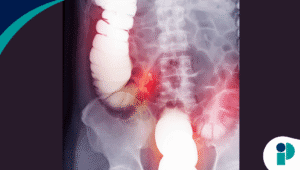

Uno de los riesgos mayores de no tratar la hepatitis C es el desarrollo de cáncer de hígado. La Dr. Ana Patricia Ortiz, investigadora principal del estudio en Puerto Rico del Centro Comprensivo de Cáncer, presentó datos alarmantes: en Puerto Rico, anualmente se diagnostican en promedio 287 hombres y 118 mujeres con esta condición, y más de 350 personas mueren cada año a causa de ella.

“La supervivencia a cinco años del cáncer de hígado es apenas del 16.5 %. Es uno de los cánceres más agresivos y mortales”, señaló la doctora Ortiz. “Pero tenemos una gran ventaja: en el caso de la hepatitis C, contamos con un tratamiento efectivo. Solo tenemos que identificar a quienes están en riesgo y actuar a tiempo”.